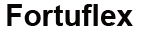

ARTROSI

Distruzione del tessuto cartilagineo. Si verifica a causa dell'insufficiente protezione della cartilagine e della mancanza di una corretta alimentazione del tessuto cartilagineo. Senza trattamento, porta alla disabilità.

GONARTROSI

Deformazione e distruzione della cartilagine del ginocchio a causa di infiammazione e malnutrizione dei tessuti. Se non curata porta alla disabiltà